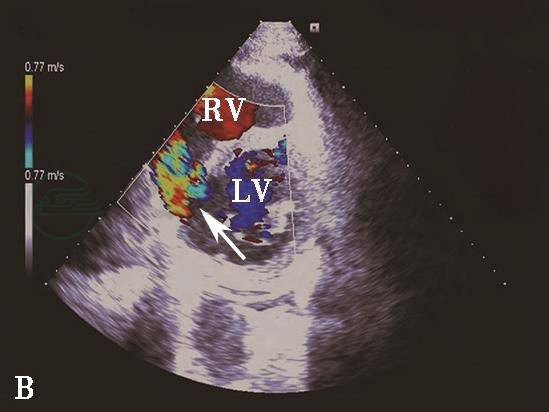

图6心肌梗死后室间隔穿孔彩色多普勒血流图像

A.彩色多普勒血流图像显示胸骨旁非标准切面室间隔心尖部穿孔处(箭头示)左向右分流信号;B.二尖瓣短轴切面后间隔基底部穿孔处(箭头示)左向右分流信号。LA.左心房;LV.左心室;RV.右心室。